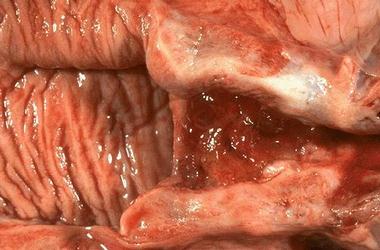

阴道是由粘膜、肌层和外膜组成的肌性管道,富伸展性,连接子宫和外生殖器,它是女性的交接器官,也是排出月经和娩出胎儿的管道。阴道常处天前后壁相接触的塌陷状态。

阴道的解剖和生理

阴道的结构及生理特点